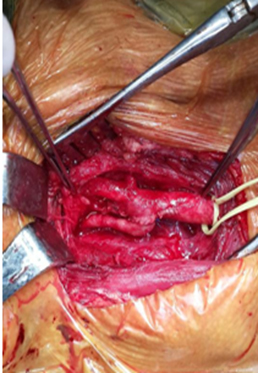

Затем с левой стороны шеи тщательно, во избежание повреждения черепномозговых нервов, произведена резекция новообразования каротидного тельца – хемодектомы (позднее подтвержденной по результатам гистологического анализа) (рисунок №2).

Рисунок №2. Процесс резекции новообразования каротидного тельца и вид после удаления.